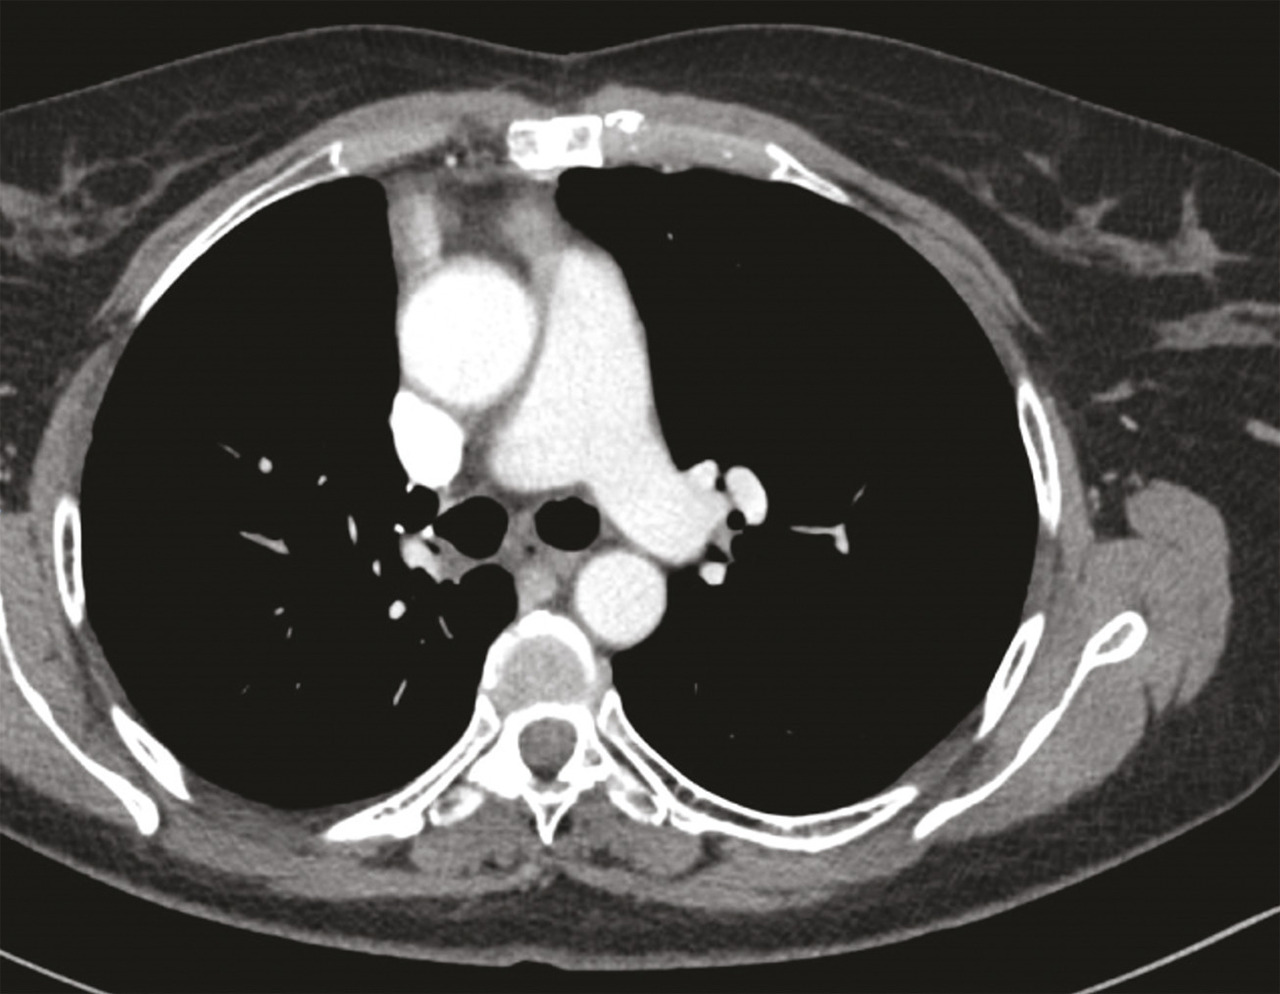

Une imagerie par résonance magnétique (IRM) du crâne réalisée 15 jours après le début des symptômes n’a pas montré d’anomalie. Toutefois, leur persistance et leur aggravation ont fait demander à son médecin traitant un dosage des anticorps antirécepteurs à l’acétylcholine, qui s’est révélé positif, conduisant au diagnostic de myasthénie. Des anticholinestérasiques ont alors été prescrits en première intention, permettant d’améliorer transitoirement les symptômes musculaires. Leur effet est de prolonger l’action de l’acétylcholine au niveau de la membrane post-synaptique par blocage réversible de l’acétylcholinestérase (deux médicaments sont disponibles : la pyridostigmine et l’ambénomium). Dans le cadre du bilan de cette myasthénie, une tomodensitométrie thoracique est pratiquée, qui met en évidence une masse médiastinale antérieure, volumineuse et polylobée évoquant une tumeur thymique (fig. 1).1

Chez cette patiente, on décide de prescrire une chimiothérapie néoadjuvante par CAP (cisplatine 50 mg/m², adriamycine 50 mg/m², cyclophosphamide 500 mg/m²). Trois cycles sont reçus, avec une bonne tolérance. L’évaluation RECIST 1.1 décrit une stabilité globale tumorale avec cependant une diminution de 10 % en taille de la lésion. La tumeur est résécable.

Une évaluation neurologique est nécessaire afin d’encadrer le geste chirurgical. Mme C. reçoit ainsi en préopératoire une injection d’immunoglobulines par voie intraveineuse afin d’éviter une exacerbation des symptômes myasthéniques en périopératoire. La chirurgie consiste en une sternotomie médiane, avec exérèse de la tumeur médiastinale et bilobectomie supérieure. Face à l’envahissement péricardique et pulmonaire adjacent, la tumeur est classée stade III (dans la classification de Masaoka-Koga), et stade T3N0M0, soit IIIA (dans la classification TNM). Les marges de résection sont saines (R0).6, 7